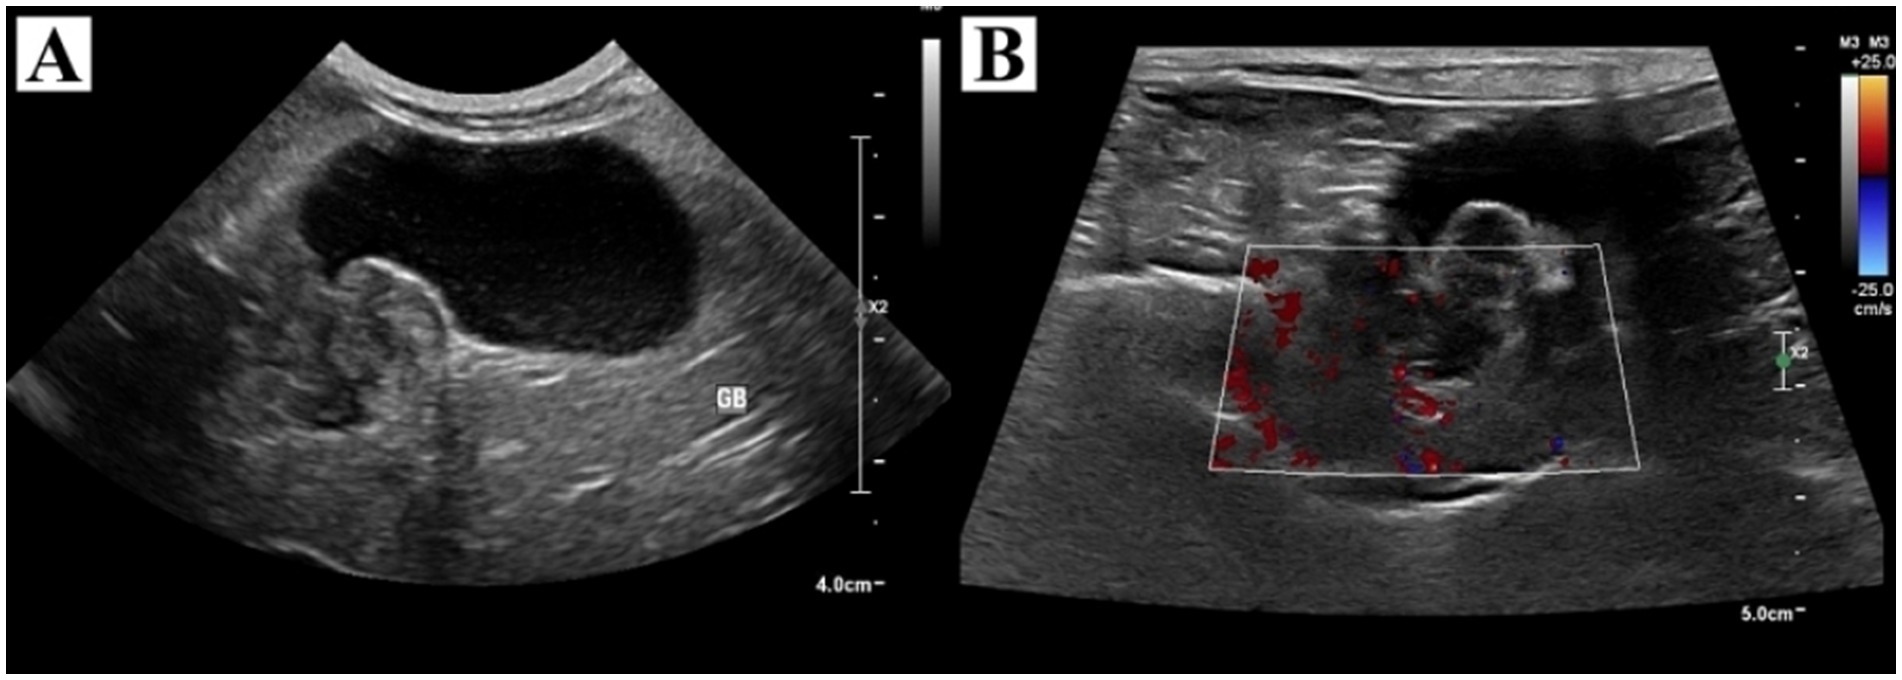

Physical examination revealed no abnormalities. Complete blood cell count, blood gas analysis, and coagulation tests showed no clinically significant abnormalities. Serum biochemistry revealed elevations in alkaline phosphatase (573 IU/L, reference range, 29–97 IU/L), aspartate transaminase (101 IU/L, reference range, 23–66 IU/L), gamma-glutamyl transferase (12 IU/L, reference range, 1–10 IU/L), and lactate (3.51 mmol/L, reference range, 0.5–2.5 mmol/L). Thoracic and abdominal radiographs revealed no abnormalities. On abdominal ultrasonography, the gallbladder was severely distended. The neck of the gallbladder appeared 1.7 × 1.5 cm, sessile, tortuous, and a heterogeneous echogenic mass was identified (Figure 1). Color Doppler imaging revealed no distinct vascularity within the mass. The common bile duct was mildly dilated. There was no evidence of metastasis on abdominal ultrasound. Preoperative CT was not performed due to the owner’s financial constraint.

Figure 1. Ultrasonographic findings of the gallbladder and tumor. (A) The gallbladder was severely distended with heterogeneous echogenic material in the neck and had no concurrent gallbladder wall thickening. (B) Color Doppler imaging revealed no distinct vascularity within the mass.

Ultrasonography is a commonly used diagnostic modality for the evaluation of gallbladder disease, however, differentiating malignant from benign lesions remains challenging due to overlapping sonographic features. In dogs, gallbladder tumors typically appeared as sessile masses with variable sizes, echogenicity, and gallbladder wall thickening. No specific ultrasonographic findings were identified to correlate with malignancy or to differentiate between different histopathologic types of tumors (4). In this case, ultrasonography revealed the sessile mass with heterogeneous echogenicity, no vascularization on Doppler imaging, and no gallbladder wall thickening. These findings are consistent with the nonspecific ultrasonographic features reported in canine gallbladder disease. Similarly, in humans, radiologic findings of an enlarged gallbladder with polypoid mass protruding into the lumen and irregularly thickened walls have been reported, but it remains difficult to distinguish leiomyosarcoma from other tumors with diagnostic imaging (1). Although advanced imaging techniques, such as 18F-fluoro-2-deoxy-D-glucose positron emission tomography/computed tomography or magnetic resonance imaging, have improved the diagnostic accuracy of sarcomas (1), further studies on the imaging evaluation of gallbladder tumors are needed.